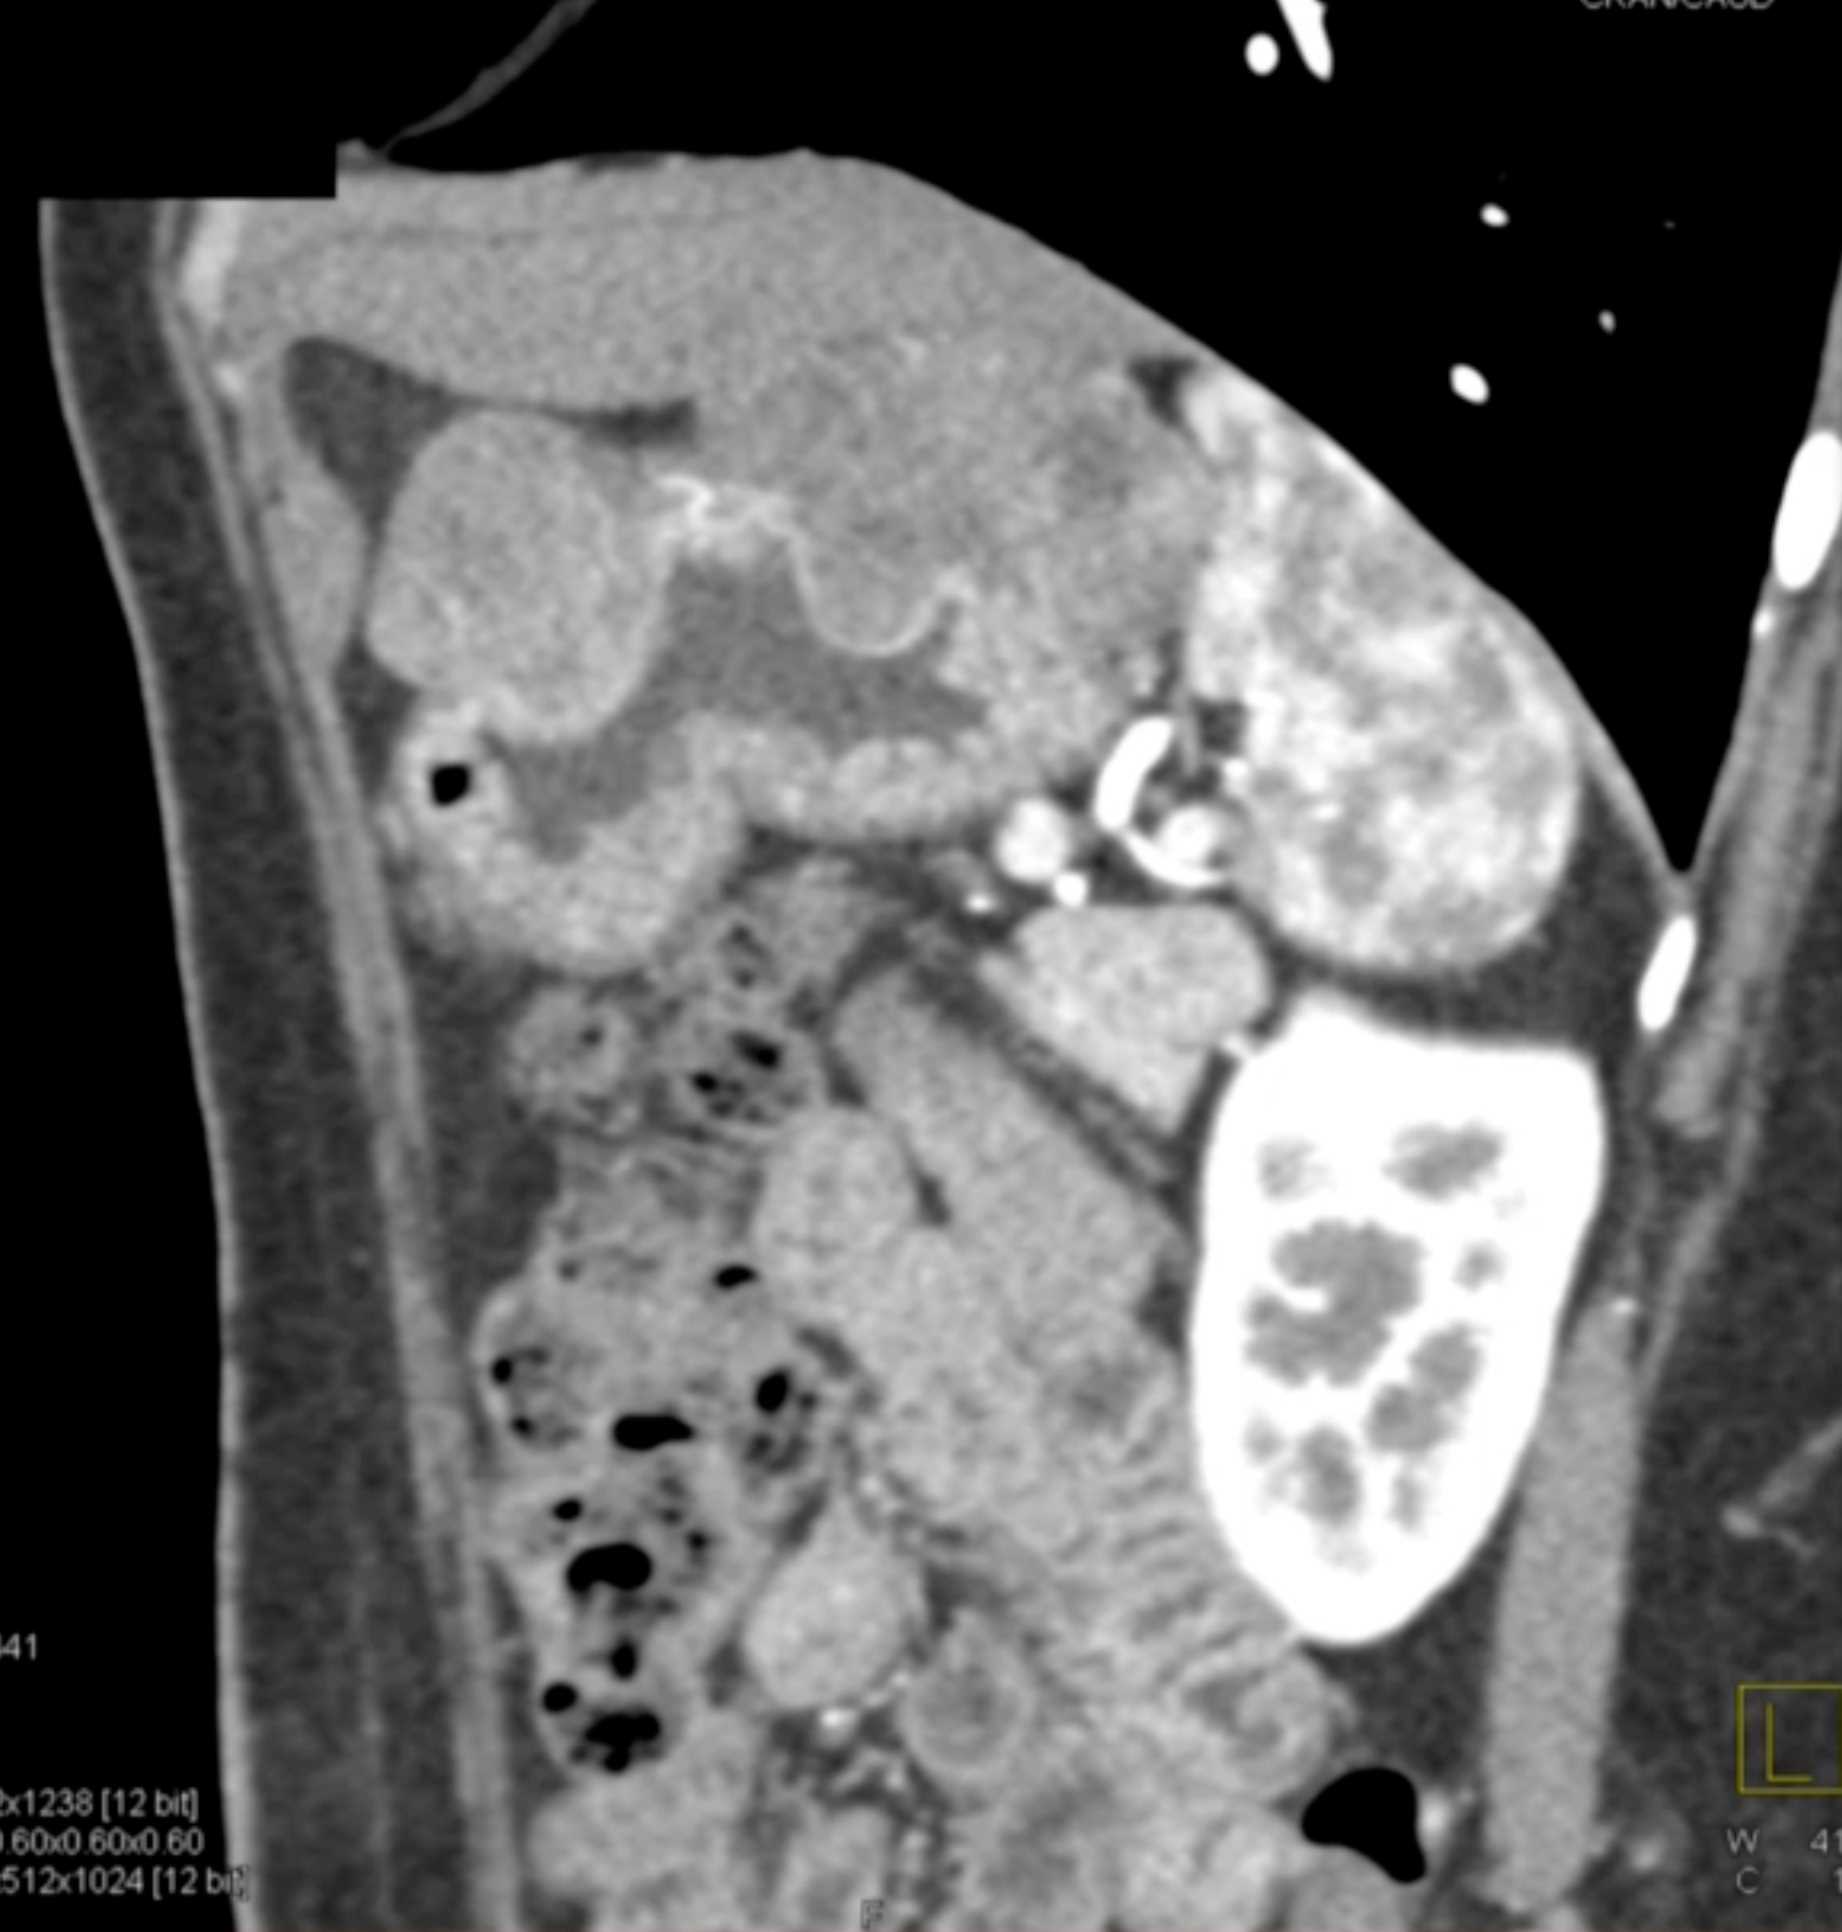

Multiple Gastric GIST Tumors with Spread to Nodes (Carney-Stratakis Syndrome)